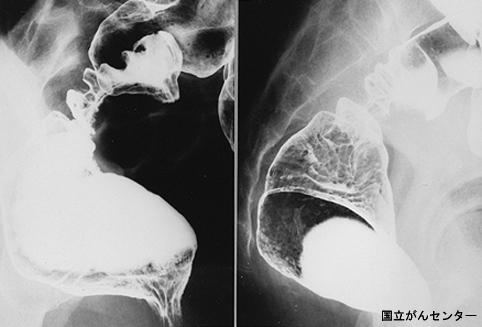

疾患(病理主体)の分類腫瘍様病変/子宮内膜症

部位(臓器別)大腸/直腸

検査方法X-P

病変の最大径(ミリ)40以上